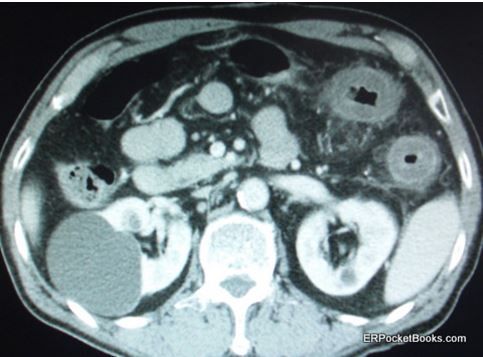

The patient has had 10 episodes of bleeding in the past 24 hours. Can you find clues to the underlying problem in the history and on the CT scan?

Figure. Cut from abdominal CT scan.

Diagnostic testing includes a complete blood cell count, metabolic panel, liver function tests, lipase test, and a CT scan of the abdomen. Laboratory values are all normal except for a potassium level of 3.1 mEq/L and a white blood cell (WBC) count of 19.2 x 103/µL. The CT scan was ordered primarily because of the elevated WBC count and one cut from that scan is shown in the Figure. (Please click on Figure to enlarge)

- What incidental abnormal finding or findings do you note?

- What abnormal finding on this CT scan correlates with this patient’s clinical presentation?